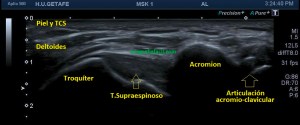

Hoy, en este breve post, te explico uno de los más importantes, que es la dinámica del Tendón del Supraespinoso para descartar el impingement por el cual se ve comprometido el normal paso del tendón del supra por debajo del espacio subacromial por una buena variedad de causas que te explica superbien aquí, es importante entender la anatomía, y también la mecánica lesional de la ecoestructura que testamos ecográficamente.

La anatomía radiológica que interviene es este estudio específico de la maniobra dinámica del tendón del supraespinoso te la dejo aquí.

Es importante tener localizado ecográficamente la articulación acromio clavicular (AAC) con la ecografía, posicionando el transductor, línea roja, como ves en esta imagen 4, donde debes cubrir toda la anatomía radiólogica explicada antes, mira:

Y lo que debes ver ecográficamente es esto: